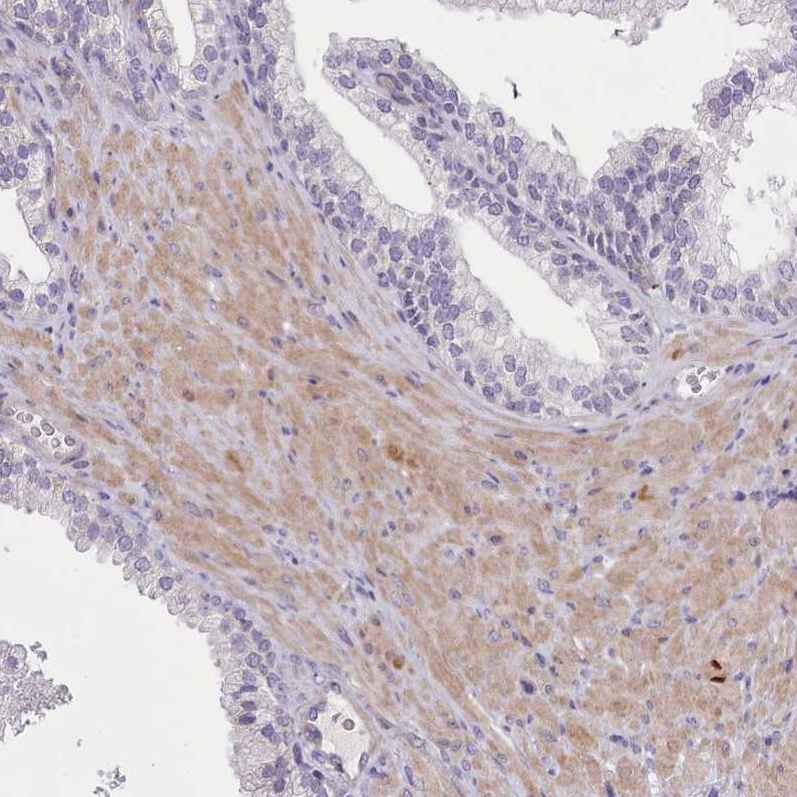

Immunohistochemical staining of human testis shows strong nuclear positivity in a subset of cells in seminiferous ducts.